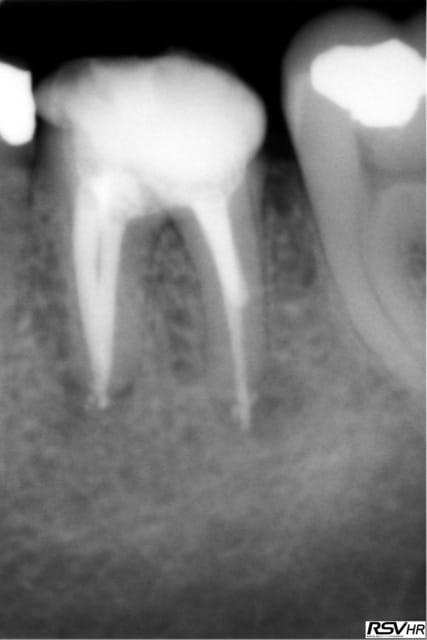

UN exemple de RTE

dépose inlay+couronne en 2009

retraitement sous digue indispensable(même sur dents antérieures la digue ce n'est pas pour faire jolie,c'est pour permettre à l'hypochlorite de rester à demeure tout le long du retraitement;il faut que çà "baigne" pour avoir une chance de

guérison apicale)

ici traitement sous hypo+digue +r-endo;il y a un dépassement léger au périapex

en 2015 guérison apparente du périapex(1h30 de retraitement!)

la dépose de l'inlay avec des ultrasons;désobturation acétate éythyle r-endo gutta compactage mac spadden

5eme photos en2009 et 2010;la dernière en 2015